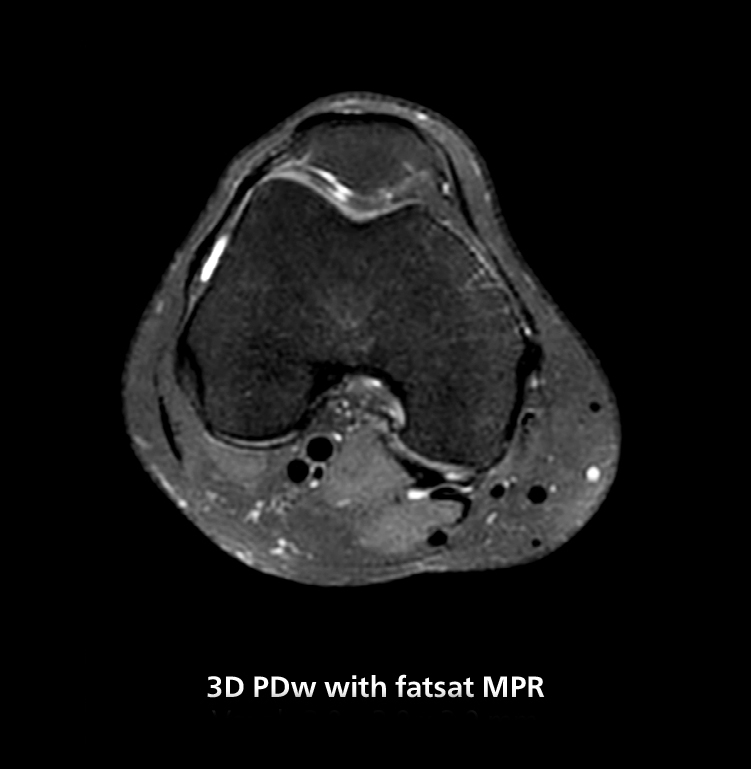

Selon le Dr Gellée, l’hôpital réalise en moyenne quatre examens par heure, soit un total de 40 à 45 patients par jour, sur le MR 5300. Les examens sont lus par environ 50 radiologues de la région de Bordeaux. Le Dr Gellée est particulièrement satisfaite de la qualité d’image du système IRM. "J’obtiens un contraste d’image plus élevé et une plus grande précision anatomique qu’auparavant”, explique-t-elle. “Dans la mesure du possible, je demande à ce que les examens soient faits sur ce système, car j’obtiens une meilleure qualité d’image anatomique. Par exemple, dans les genoux, je peux obtenir de superbes images du ménisque. Pour moi, les images sont aussi belles qu’avec un système 3T.”

La séquence 3D isotrope haute résolution de cet exemple d’IRM permet un reformatage pour obtenir d’autres orientations de haute qualité. Acquise sur le système MR 5300.

“Les séquences 3D sont plus rapides”, affirme le Dr Gellée. “Avec Compressed SENSE, nous pouvons remplacer deux ou trois acquisitions 2D par une acquisition 3D de haute qualité. Des orientations supplémentaires de haute qualité peuvent être obtenues par post-traitement de l’ensemble des données 3D, ce qui permet d’économiser du temps d’acquisition.”